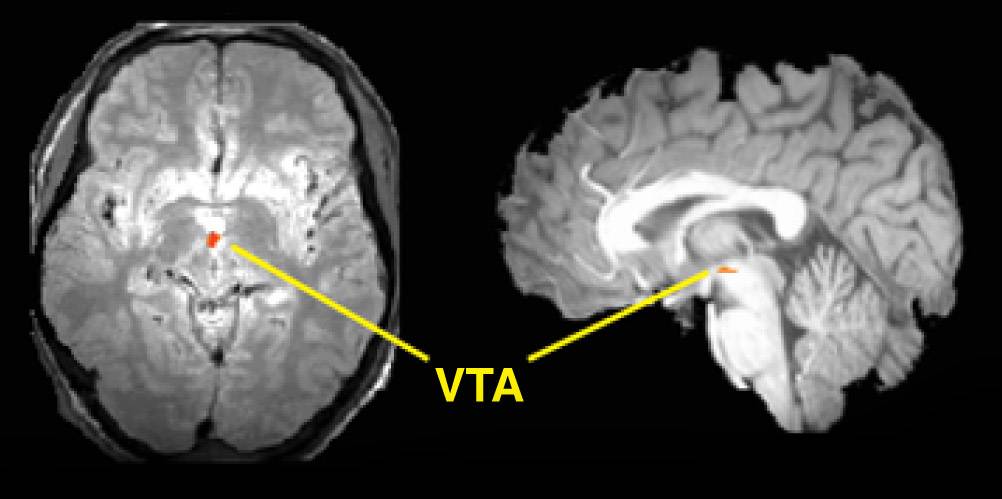

Horizontal (left) and vertical (right) slices of brain show increased blood flow (red region) in brainstem (VTA or ventral tegmental area) in measurements made by functional magnetic resonance imaging.

Reporting in the Feb. 28 edition of Science, the scientists describe using functional magnetic resonance imaging to study brainstem activity in dehydrated humans. The scanning technique allows researchers to watch the brain in action.

The team was able to develop high-resolution images that tracked the activity of tiny clusters of dopamine neurons. They weeded out distortions caused by many pulsing blood vessels in the brainstem. They also employed computerized rules of thumb known as algorithms and imaging techniques to reduce the effects of head movement and combine images from different subjects.